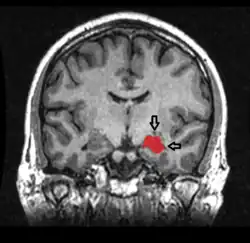

![]() El hipocampo está localizado en la parte medial del lóbulo temporal del cerebro. En esta vista lateral del cerebro humano, el lóbulo frontal está a la izquierda, el lóbulo occipital a la derecha, y los lóbulos temporal y parietal han sido retirados en gran medida para revelar el hipocampo subyacente. | ||